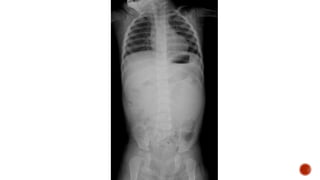

Frontal chest radiograph shows few ill defined patchy opacities in both the lung

fields, few of them showing cavitatory changes. TCC seen in situ.

Compared to the previous radiograph there is reduction in the number of opacities

with cavitatory changes.

 Malignancy:

 Squamous cell carcinoma of the lung

 Metastasis :

 squamous cell ca

 adenoca from GIT/breast

 sarcoma

 cervical carcinoma

 urothelial carcinoma of the bladder